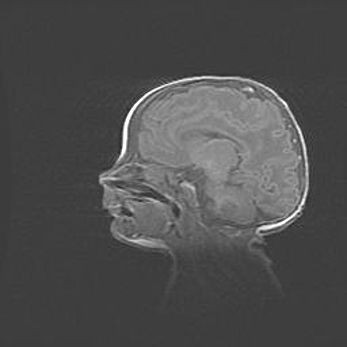

Аномалия Денди-Уокера. Признаки гипоплазии мозолистого тела.

Возраст: 5 месяцев 3 дня

Вес: 5550 г

Пол: мужской

Окружность головы: 39 см

Срок гестации: 40 недель

Аномалия Денди-Уокера – это порок развития головного мозга, для которого характерна триада симптомов: гипотрофия или аплазия червя мозжечка и/или полушарий мозжечка, расширение четвёртого желудочка с формированием ликворной кисты задней черепной ямки, гипертензионная гидроцефалия различной степени.

Гипоплазия мозолистого тела относится к дефектам внутриутробного этапа развития мозговой ткани, возникающим в процессе закладки структур головного мозга, что происходит на начальных этапах развития эмбриона.